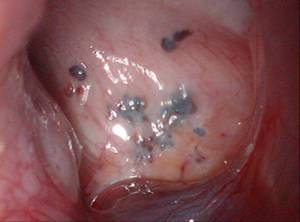

腹腔镜检查:目前内异症诊断的金标准,即腹腔镜下在盆腔腹膜上见到一些紫蓝色、暗红色或者白色的结节,需结合策划病理学结果,病灶中可见子宫内膜腺体和间质即可确诊(下图)。

图:腹腔镜下的内异症病灶